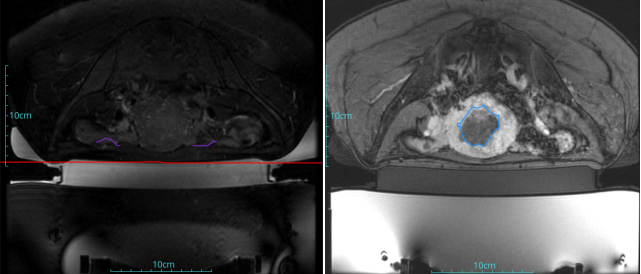

子宮腺肌癥

患者信息:女,38

診斷:子宮腺肌癥

病灶尺寸:約為40*37*40mm

ROT深度:病灶的ROT中心距離皮膚45mm

術后評估:術后造影增強圖像顯示消融區(qū)域(右側)與病灶區(qū)域(左側)重合度較好,非灌注區(qū)域連續(xù)且一致。

結論:對該病灶具有非常好的消融效果,治療過程中,溫度上升曲線符合預期,每個被治療的靶點240CEM區(qū)域體積較大、外形飽滿、連續(xù)。病灶消融良好,NPV體積比約80.6%。